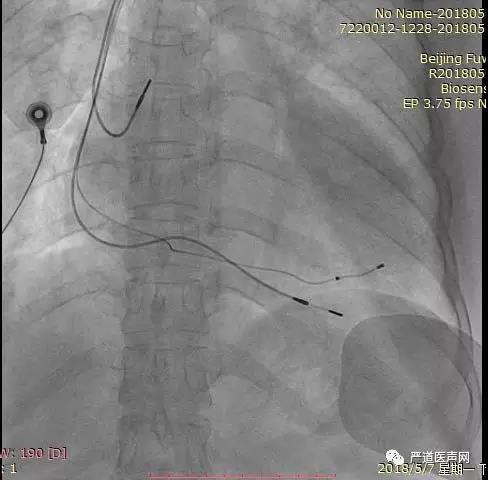

首先进行冠状静脉球囊造影,显示血管较细,预计导线通过困难,考虑可能近段有侧枝或血管未显示,于是在无球囊的情况下再次造影,未发现合适血管。决定尝试近段血管,导丝顺利通过, 但由于靶静脉狭窄,反复尝试电极无法进入,随后深插鞘管以增加支撑力,导丝进入较高分支,电极仍无法进入。于是尝试前侧血管,导丝通过后,电极仍然无法通过。重新分析造影后,尝试后静脉或心中静脉血管, 回撤鞘管至窦口处,保留原PTCA导丝作为支撑,使用另一根PTCA导丝探入心中静脉,尝试送入电极,由于靶静脉开口处扭曲电极依然无法进入。随后使用鞘中鞘在侧枝开口作为支撑,在鞘中鞘支撑下左室电极进入靶静脉, 尝试把电极往深处送,测试左室导线参数良好,阈值Tip端阈值1.5V/0.4ms,5V无膈神经刺激。最后植入右房、右室电极。

AP

LAO 30°

RAO 30°

术后最终影像

如果心中静脉有理想的左侧侧支,可以作为左室导线的靶静脉。使用鞘中鞘有助于顺利植入导线。